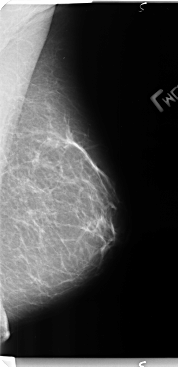

B_3136_1.RIGHT_MLO

B_3136_1.LEFT_CC

LEFT_MLO LINES 4760 PIXELS_PER_LINE 2304 BITS_PER_PIXEL 12 RESOLUTION 50 NON_OVERLAY

LEFT_CC LINES 4768 PIXELS_PER_LINE 2464 BITS_PER_PIXEL 12 RESOLUTION 50 NON_OVERLAY